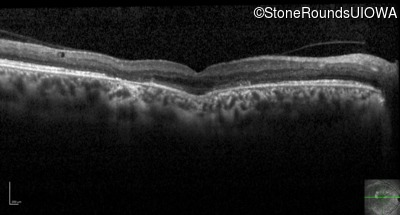

Optical Coherence Tomography - Left - 20/25 -1

Exemplar / OCT Stack

OCT Stack